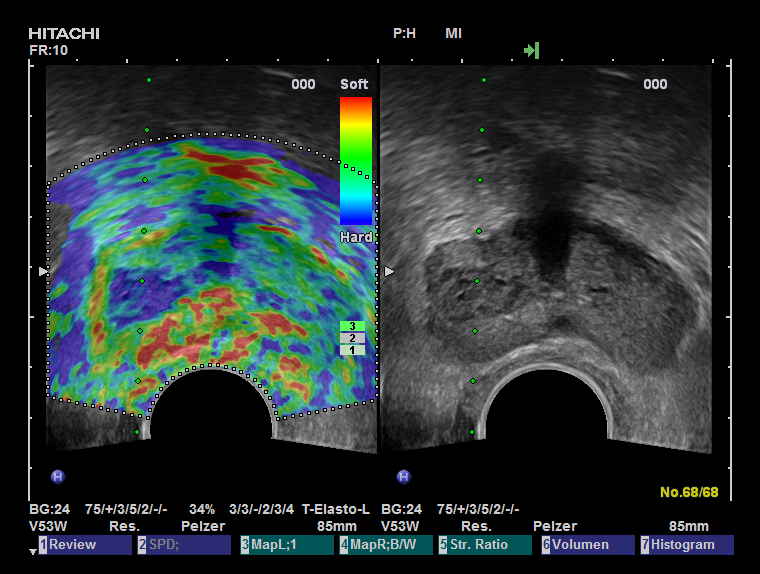

Die Methoden Ultraschall-Elastographie, der farbkodierte Doppler-Ultraschall sowie der kontrastmittelverstärkter Ultraschall und insbesondere die Echtzeit-MRT-Ultraschall-Fusion können helfen, auffällige Gebiete in der Prostata aufzuzeigen. So kann zum Beispiel ein in einer MRT (Magnetresonanztomographie) gefundener suspekter (also auffälliger) Bereich ganz gezielt biopsiert werden und auch zusätzlich noch elastographisch untersucht werden. Dies ist während einer herkömmlichen MRT-Untersuchung nicht möglich.

Eine multimodale Prostataabklärung erlaubt uns, die Prostata mittels modernster Verfahren zu untersuchen. Hierbei kommen verschiedene Untersuchungsmethoden zur Anwendung. Insbesondere die Echtzeitelastographie oder die kontrasmittelunterstützte Untersuchung der Prostata können hierbei wichtige Erkenntnisse über die Beschaffenheit der Prostata beisteuern. Auffällige Areale können in Echtzeit schmerzfrei mit lokaler Betäubung abgeklärt werden. Als Besonderheit können diese modernen Methoden auch mit einer bereits durchgeführten MRT-Untersuchung der Prostata fusioniert werden. Das bedeutet, in einer MRT gefundene auffälligen Areale der Prostata können zusätzlich mit modernsten Ultraschalluntersuchungen kombiniert untersucht werden und dann auch gezielt mittels gezielter Prostatabiopsie abgeklärt werden. Diese Untersuchung ist dann multimodal (zB Elastographie + konventionellem Ultraschall + MRT-Fusion).

Eine multimodale Prostataabklärung erlaubt uns, die Prostata mittels modernster Verfahren zu untersuchen. Hierbei kommen verschiedene Untersuchungsmethoden zur Anwendung. Insbesondere die Echtzeitelastographie oder die kontrasmittelunterstützte Untersuchung der Prostata können hierbei wichtige Erkenntnisse über die Beschaffenheit der Prostata beisteuern. Auffällige Areale können in Echtzeit schmerzfrei mit lokaler Betäubung abgeklärt werden. Als Besonderheit können diese modernen Methoden auch mit einer bereits durchgeführten MRT-Untersuchung der Prostata fusioniert werden. Das bedeutet, in einer MRT gefundene auffälligen Areale der Prostata können zusätzlich mit modernsten Ultraschalluntersuchungen kombiniert untersucht werden und dann auch gezielt mittels gezielter Prostatabiopsie abgeklärt werden. Diese Untersuchung ist dann multimodal (zB Elastographie + konventionellem Ultraschall + MRT-Fusion).

Die Echtzeit-Elastographie ist eine Messung der Elastizität des Prostatagewebes. Dies ist ein bildgebendes Verfahren, mit dem tumorverdächtiges Gewebe in der Prostata mittels verschiedenen Farben auf dem Ultraschallmonitor angezeigt wird. Dabei misst die Ultraschall-Elastographie die Elastizität des Gewebes, also die Härte des Prostatagewebes indem es die Reaktion des Gewebes auf Druck misst. Tumorgewebe ist in der Regel härter als gesundes Gewebe. Die harten tumorverdächtigen Areale werden so aufgespürt und können sofort gezielt biopsiert werden. Die Ultraschall-Elastographie erzielt beim Aufspüren von Tumorbereichen in der Prostata deutlich aussagekräftigere Ergebnisse als der herkömmliche Ultraschall.

Zunächst einmal werden die bereits durchgeführten und von Ihnen mitgebrachten MRT-Bilder (1,5T-3T, mit/ohne rektale Spule, DICOM-Format) in unser Gerät eingelesen. Anschließend werden die suspekten Areale und die Organgrenzen der Prostata in der MRT-Bildgebung markiert. Nun beginnt der praktische Teil: In angenehmer Seitenlage wird über einen modernen transrektalen Ultraschall die Prostata aufgesucht und anhand der Anatomie der Prostata mit dem MRT Bild fusioniert. Der Untersucher sieht nun auf der linken Seite des Flachbildschirmes des Ultraschallgerätes das Original-MRT-Bild mitsamt des Markierungen und auf der korrespondierenden rechten Seite die Live Ultraschallbilder in denen die Markierungen der MRT-Untersuchung zu sehen sind. Die auffälligen Areale können nun einer Elastographie oder einer Kontrastmittel-Untersuchung unterzogen werden um den Grad der Auffälligkeit zu bestimmen. Auf Wunsch können auch jetzt gleich die Biopsien durchgeführt werden.